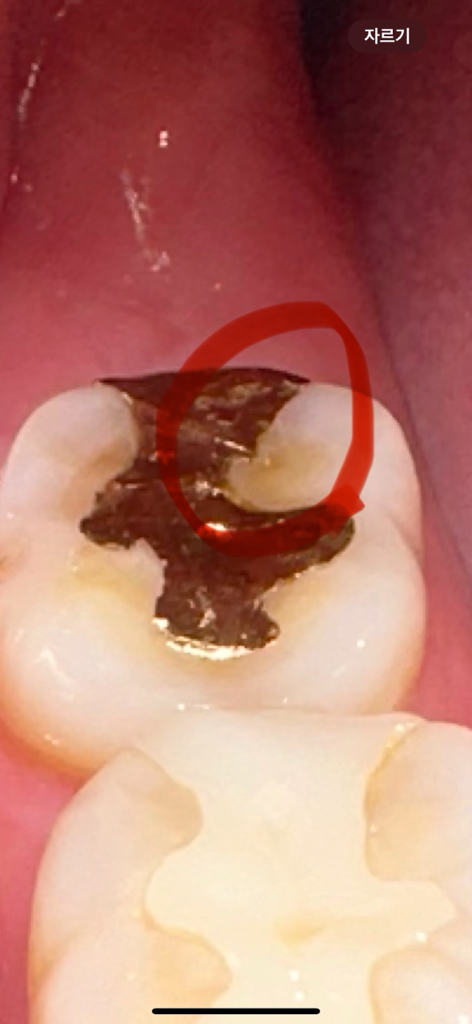

보철물을 다듬었는데 딱딱한게 씹혔는데 그게 음식인지 보철물 일부가 떨어져나간건지 모르겠어요 ㅠㅠ 위에가 오늘이고 밑에가 어제 입니다 ㅜㅜ 오늘 딱딱한게 씹혀서 찍어보니 뭔가 살짝 모양이 바뀐것같기도해서요.. 일부만 떨어져 나가는 경우도 있나요?

• 2번 째 사진

보철물이 일부만 떨어져 나가는 경우도 있습니다. 사진상으로는 떨어진 것이 확실해보이진 않습니다.

치아가 살짝 깨진거 같습니다. 음식물이 끼신다면 가셔서 저부위만 살짝 때워달라고 하세요.

일부만 깨져서 떨어나가는 경우도 있을 수 있습니다 다만 사진상으로는 크게 차이가 나는 부분이 없습니다

보철물이 일부만 탈락될수도 있습니다. 탈락된부위에 추가적인 충치 유발가능성이 있기에 치과에 방문하여 다시 치료를 받길 권합니다.